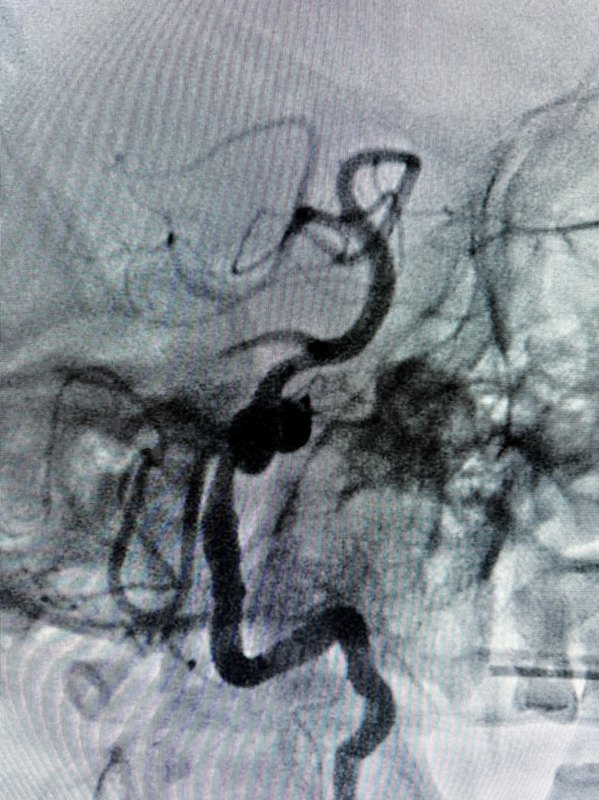

經(jīng)橈動(dòng)脈遠(yuǎn)端分支入路血流導(dǎo)向裝置栓塞椎動(dòng)脈V4段夾層動(dòng)脈瘤,“雙”顱內(nèi)支撐導(dǎo)管建立通路,柔順性與支撐性兼顧,穩(wěn)定的通路是迂曲血管路徑下手術(shù)成功的前提?。?!